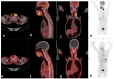

Materials and methods: In this prospective cross-sectional study, twenty-three (23) patients aged 52.9 ± 10.4 (19.6), 17 males and 6 females with primarily diagnosed (n = 17) or pre-treated (n = 6) SCC of the oral cavity (OCSCC, n = 11), oropharynx (OPSCC, n = 9), nasopharynx (NPSCC, n = 2) and unknown primary (n = 1) underwent imaging with [68Ga]Ga-Pentixafor-PET/CT. In 16/23 patients 2-[18F]fluoro-2-deoxy-D-glucose ([18F]F-FDG) served as a standard reference. All lesions were visually rated using a 5-point Likert scale. For both tracers, maximum standardized uptake values (SUVmax) and the total lesion uptake (TLU) were recorded and compared using the Wilcox-signed rank test. In addition, the tumor-to-background ratios were derived using the liver (TLR), spleen (TSR), and posterior cervical muscles (TMR) as background. The relationships between the SUVs of the two tracers were assessed using the Spearman correlation. CXCR4 immunohistochemistry (IHC) staining was correlated with 68Ga-Pentixafor-PET/CT in 21/23 patients.

Results: Ninety-one percent (21/23) of tumors were visually detected on [68Ga]Ga-Pentixafor; however, [68Ga]Ga-Pentixafor was less intense compared with [18F]F-FDG-PET. Quantitative analysis showed higher [18F]F-FDG SUVmax in comparison with [68Ga]Ga-Pentixafor (16 ± 6.7 vs. 5.8 ± 2.6 g/mL, p = 0.011) and SUVmean (9.3 ± 4.1 vs. 3± 1.6 g/mL, p < 0.001) and TBR 4.9 ± 2.3 vs. 2.36 ± 1.4 p = 0.014. Nasopharyngeal cancer demonstrated more intense tracer accumulation than oropharyngeal and oral cavity malignancies. CXCR4 IHC staining was positive in 15/21 patients, and there was a statistically significant correlation between IHC staining and [68Ga]Ga-Pentixafor SUVmean r = 0.5 p = 0.027, and performance status r = 0.83 p = 0.0104.

Conclusions: In conclusion, although [68Ga]Ga-Pentixafor cannot replace [18F]F-FDG as a diagnostic tool because of its lower avidity, the correlation between CXCR4 targeted 68Ga-Pentixafor PET imaging and CXCR4 IHC staining indicates the potential of 68Ga-Pentixafor as an effective tool for selecting patients who may benefit from therapies targeting CXCR4. In addition, [68Ga]Ga-Pentixafor has no physiological brown fat uptake, which often obscures cervical lesions on [18F]F-FDG PET/CT imaging.